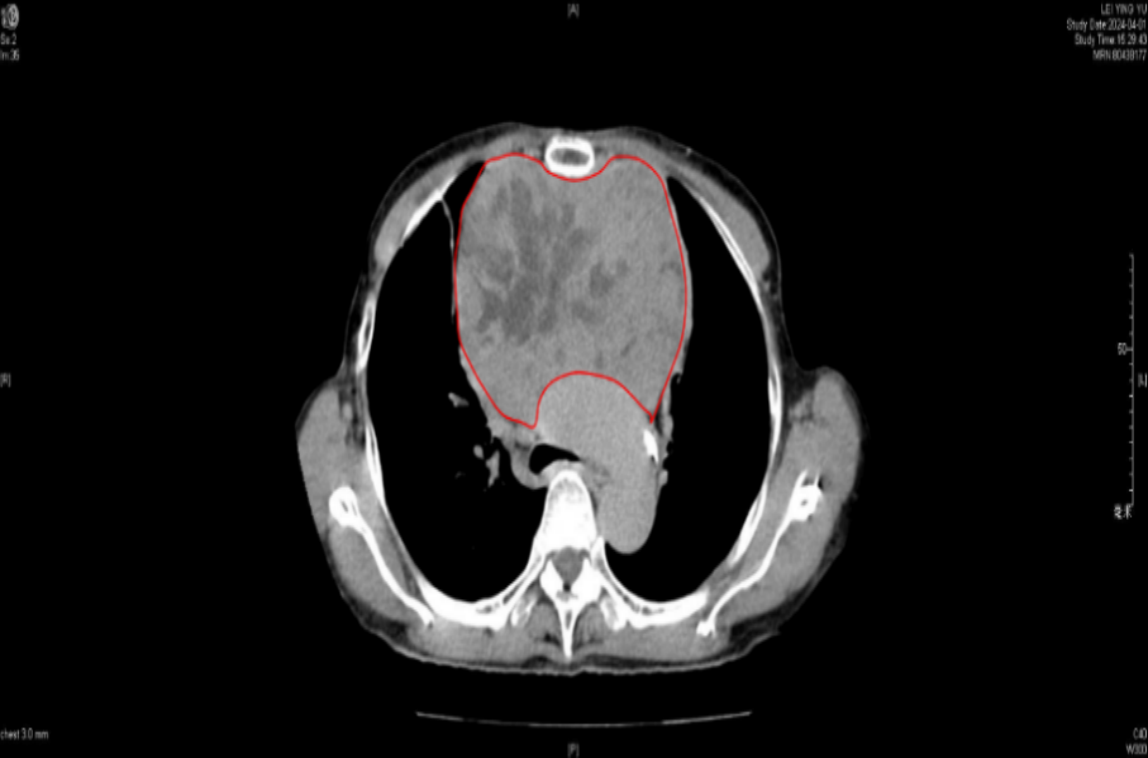

被咳嗽、胸闷折磨多日不见好转,家人带着雷婆婆来到医院检查——胸腔里竟然长了个超过14厘米的巨大肿块!这个硕大无比的肿物就像一个“巨石”顶住雷婆婆的胸口,还压迫了心脏和气管!

红色画圈部分为肿块

终于找到了“元凶”,雷婆婆的家人们心急如焚,随即找到我院胸外科副主任陈文树求助。陈文树为雷婆婆完善了检查,在进行纵隔穿刺活检后,通过病理确诊——这是A型胸腺瘤,是发生于胸腺的原发性肿瘤,也是前纵隔最常见的肿瘤类型。